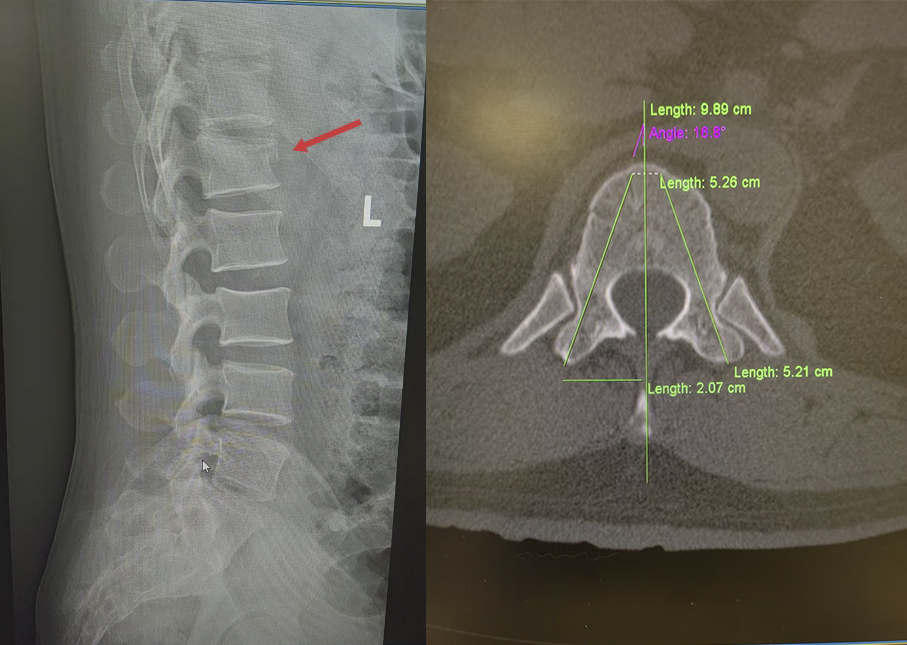

湖北日报讯(记者汪菁华、通讯员林国山)近日,45岁的周先生(化姓)从约3米高处意外坠落,臀部首先着地,当即感到腰骶部剧烈疼痛。情况紧急,他随即被送往武汉大学泰康临床学院/泰康同济(武汉)医院创伤外科,诊断为腰1椎体压缩性骨折。

患者伤情影像

针对伤情,武汉大学泰康临床学院/泰康同济(武汉)医院创伤外科主任张俊与骨科主任姚士军迅速组建救治团队,对影像学资料进行详细研判,结合患者高血压病史,综合评估骨折稳定性及神经受压风险。经讨论,团队决定采用经皮椎弓根钉棒复位内固定术。该术式属微创范畴,可在实现骨折复位固定的同时,最大限度减少对腰背部肌肉及软组织的损伤,有利于患者术后早期功能锻炼及快速康复。

3月12日,手术按计划进行。术中,在C臂机透视引导下,主刀医生张俊主任于患者腰背部选取1.5至2厘米的微小切口,经导针准确定位椎弓根,依次置入螺钉及连接棒,并对压缩椎体进行撑开复位。术中X线检查显示,骨折复位满意,内固定物位置良好。整场手术历时近3小时,过程顺利。